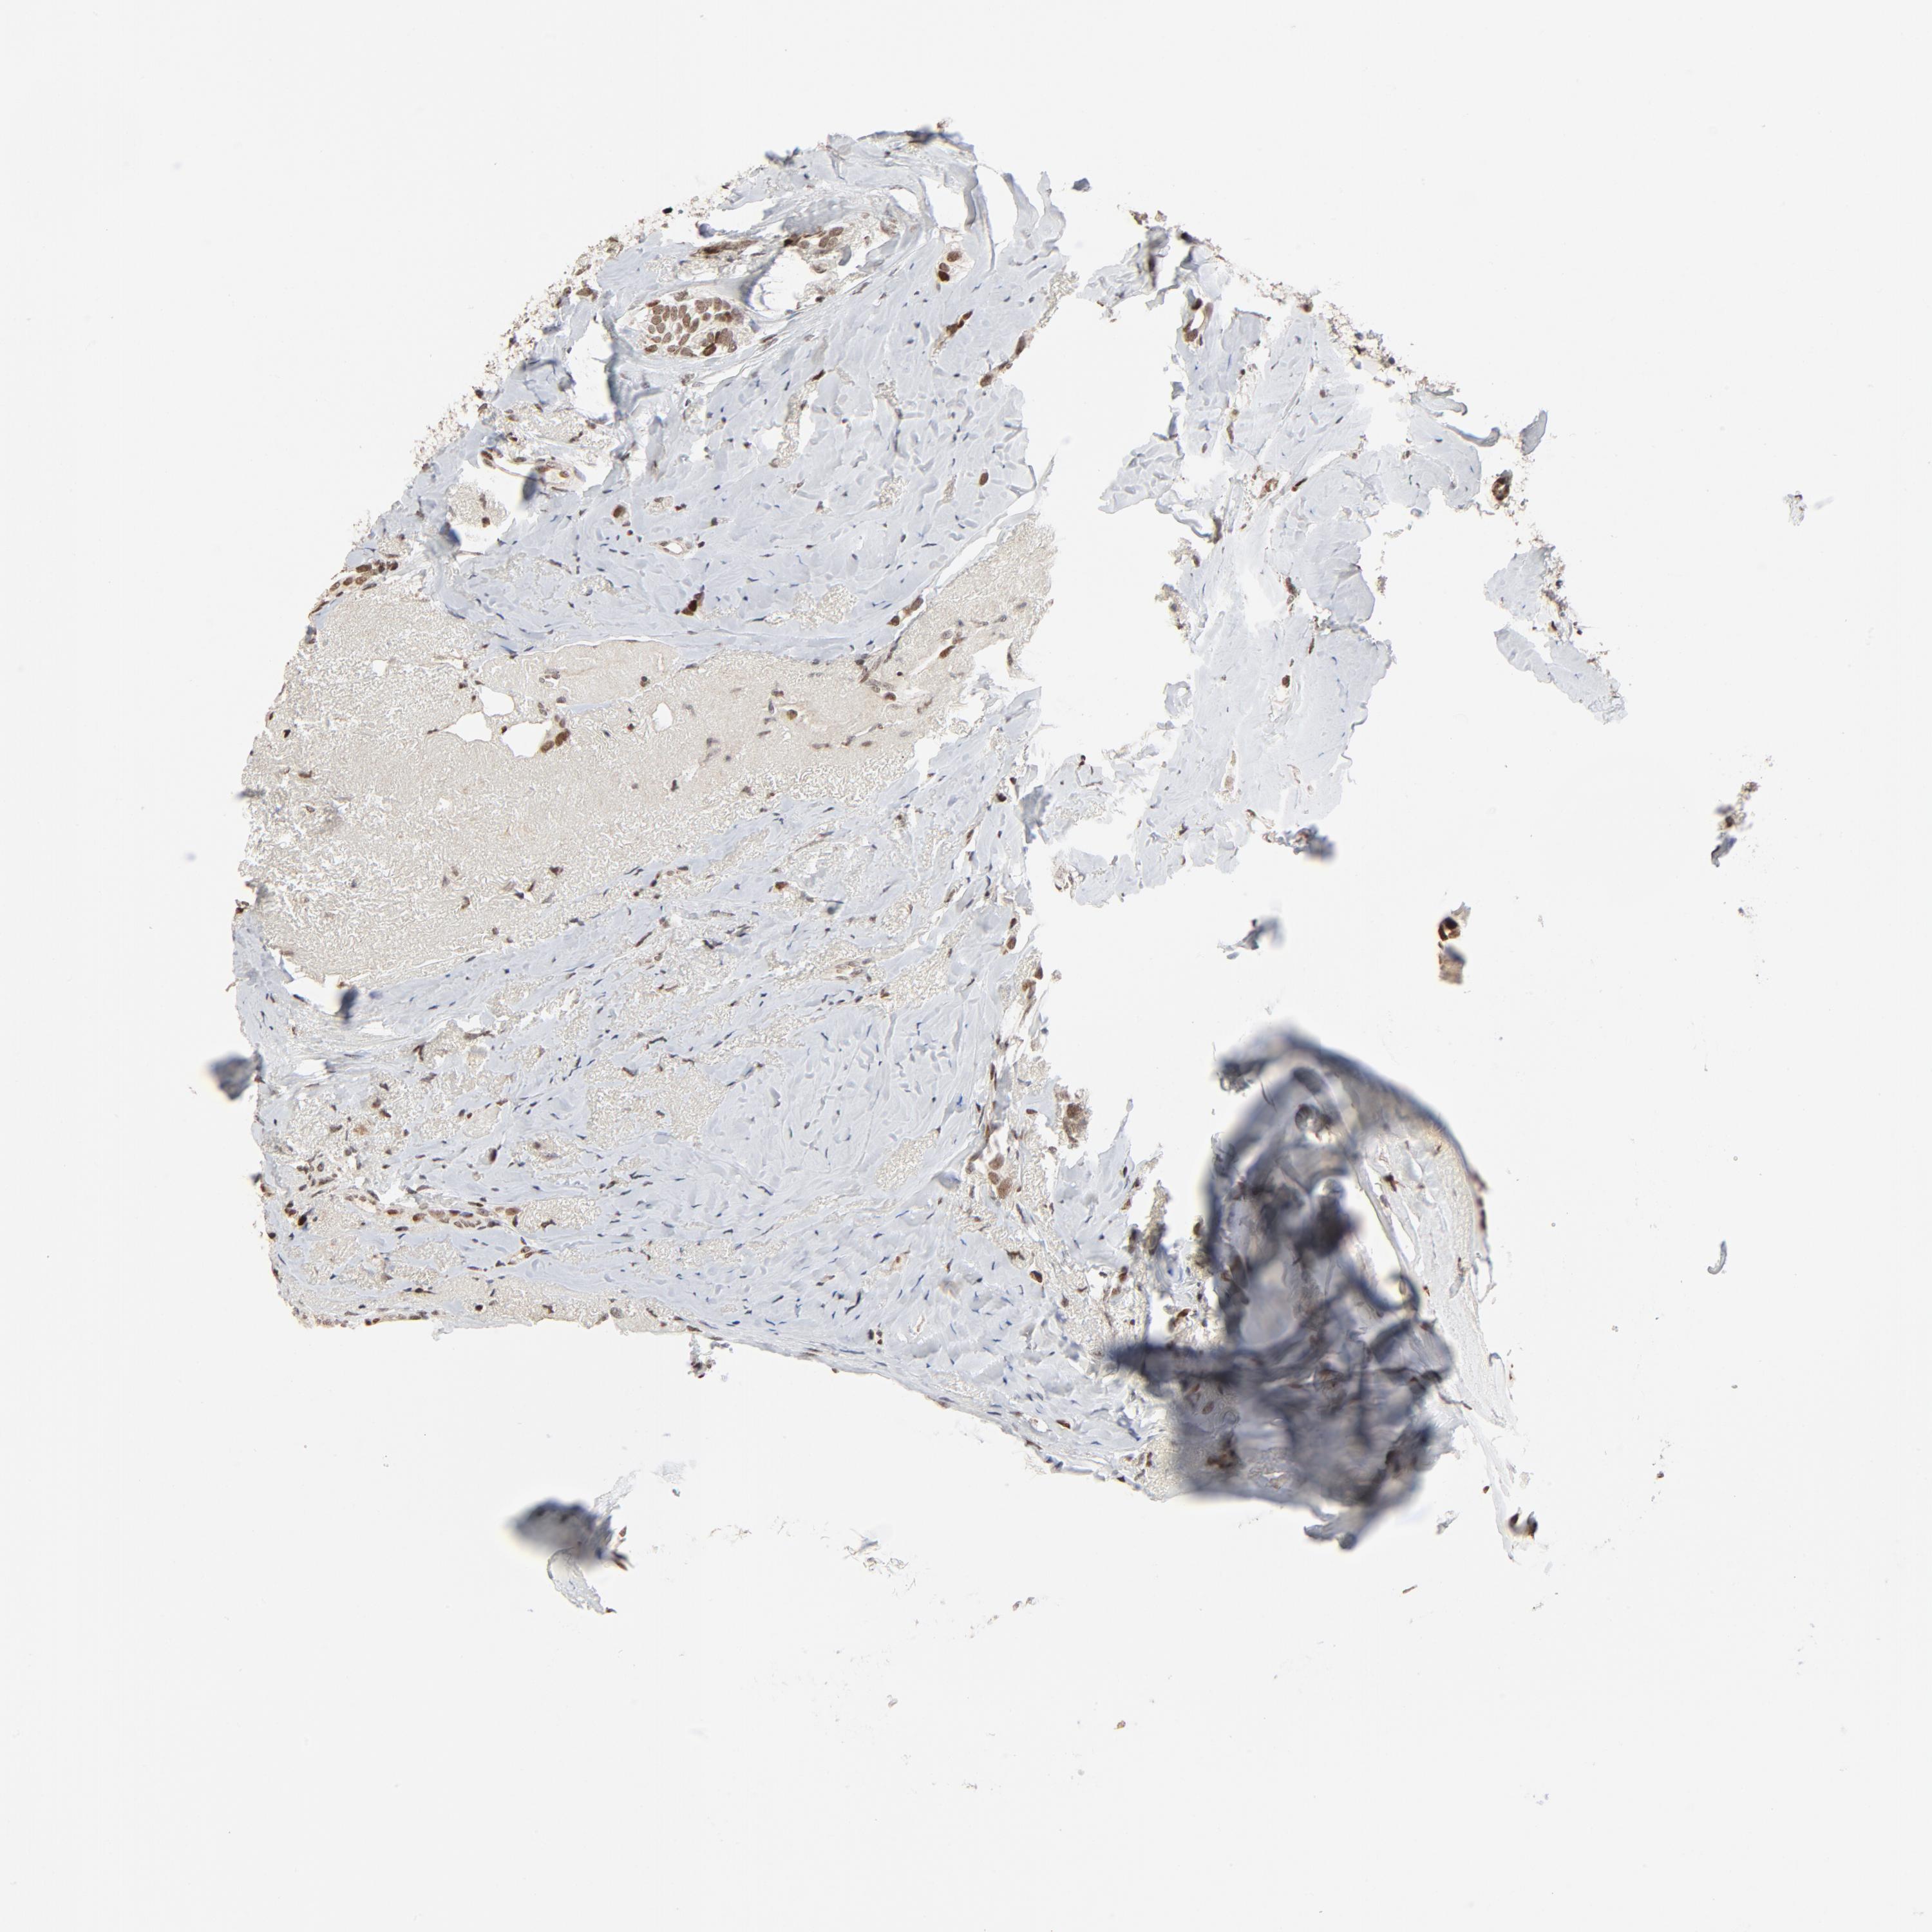

BRCA TCGA BRCA VALIDATION PROTEIN EXPRESSION

Breast cancer

Human cancer